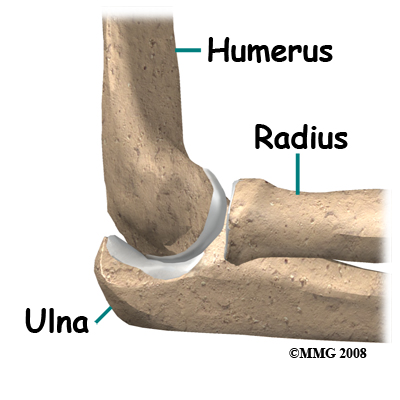

The bones of the elbow are the humerus (the upper arm bone), the ulna (the larger bone of the forearm, on the opposite side of the thumb), and the radius (the smaller bone of the forearm on the same side as the thumb).

The elbow itself is essentially a hinge joint, meaning it bends and straightens like a hinge. But there is a second joint where the end of the radius (the radial head) meets the humerus. This joint is complicated because the radius has to rotate so that you can turn your hand palm up and palm down. At the same time, it has to slide against the end of the humerus as the elbow bends and straightens.

The joint is even more complex because the radius has to slide against the ulna as it rotates the wrist as well. As a result, the end of the radius at the elbow is shaped like a smooth knob with a cup at the end to fit on the end of the humerus. The edges are also smooth where it glides against the ulna.